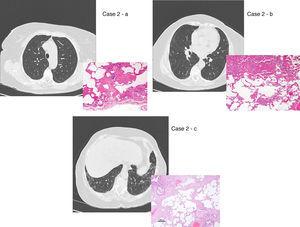

There are two aspects that may raise doubts in the HRTC interpretation: the distinction between honeycombing and traction bronchiolectasis and fibrosis with emphysema. The differential diagnosis is a challenge even for an experienced radiologist.47, 49, 50 The 2011 ATS/ERS/JRS/ALAT multidisciplinary consensus1 stated that the identification of four typical findings establishes the definite diagnosis of UIP: 1 – subpleural and basal lung lesions predominance; 2 – reticulation; 3 – honeycombing with/without traction bronchiectasis/bronchiolectasis; 4 – absence of findings that do not support a UIP pattern (Table 2, Table 3; Figure 2).

Figure 2. UIP/IPF identification in HRCT and histopathology. Case 1 – a: Common histopathological features of UIP/IPF consisting in honeycombing as a result of subpleural airway spaces confluence with bronchialization of epithelium where mucus cells may be predominant. HE 100×. Case 1 – b: The previous image aspects are revealed by higher production of mucus occupying the new formed subpleural smaller confluent airspaces. HE 100×. Case 1 – c: The interstitium intermingling honey-combing loses elastin fibres and is represented by fusiform cells, either fibroblasts or miofibroblasts, with collagen deposition. Elastin-van Gieson 100×. Case 2 – a: Irregular confluent air spaces with typical subpleural localization of UIP/IPF honeycombing with interstitium enlargement by fusiform cells. HE 100×. Case 2 – b: The adjacent lobular parenchyma accentuate histopathological heterogeneity, starting by overinflation and pseudo emphysema morphology. HE 100×. Case 2 – c: The lobular histopathological remodelling aspect of fibrosis enlarging alveoli septae till central bronchiolo-vascular axes and alveolar bronchialization. HE 100×. Case 3 – a: Small subpeural confluent air-spaces with bronchial-like epithelium and juvenile foci of fibroblasts in myxoid matrix; lymphocytes are seen. PAS 200×. Case 3 – b: UIP/IPF heterogeneous morphology in airspaces confluence with subpleural preponderance and committing the whole lobule. HE 100×.

The histological pattern of UIP must present: 1 – marked fibrosis/architectural distortion, with or without honeycombing in a predominantly subpleural/paraseptal distribution; 2 – patchy involvement of lung parenchyma by fibrosis; 3 – fibroblast foci; 4 – absence of features against a diagnosis of UIP suggesting an alternate diagnosis1, 51 (Figure 2).